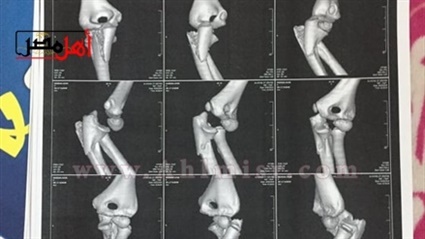

يقول أيسر فاروق والد الضحية، بدأت أزمة ابنتي حينما ورد إلى إتصال هاتفى من المدرسة الخاصة التى تدرس بها، ليخبروني بأنها سقطت فى المدرسة وأصيبت بكسر فى الذراع، ذهبت مسرعا إلى المدرسة وذهبت إلى خمس أطباء، واكتشفنا أن المفصل مخلوع والعظم مفتت ويحتاج إلى عملية كبيرة بسبب سقوط كبير تعرضت له ابنتي، لافتا إلى أن أحد الأطباء أخبرني أن السقوط الذى تعرضت له الطفلة سقوط كبير نظرا لأن وزن الطفلة لا يتناسب مع السقوط الذي تعرضت له لذا حدث تفتت بالعظام، مشيرا إلى أنه تم إجراء العملية الجراحية لابنتي واستخدم الأطباء الجبس والسلك نظرا لوجود تفتت بالعظام وهى ما يعد إحداث عاهة مستديمة.واستكمل، فقدت نجلتي النطق تماما لمدة 20 يوما وعلمنا من زملائها أن اثنين من زملائها بالمدرسة قاما بإسقاطها من الدور الثاني كانا هاذان الزميلان قاما بالتعدي بالضرب على ابنتي لعدة مرات فضلا عن سرقتهما لسندوتشات وعصائر ابنتي وقمت بالاستغاثة بالمدرسة.